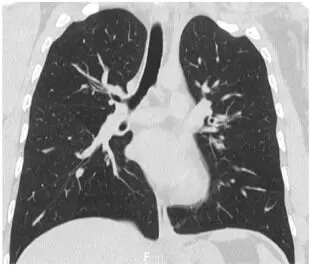

A 33-year-old Japanese woman with bronchial asthma since age three was treated with fluticasone propionate plus salmeterol twice daily after several asthma exacerbations at age 17. Her course was complicated by chronic eosinophilic pneumonia at age 33 which resolved without the need for systemic steroids. However, in the four months following resolution of her chronic eosinophilic pneumonia, the patient had three asthma exacerbations, and a recurrence of chronic eosinophilic pneumonia, with blood leukocytes of 8500/µL, of which 25.0% were eosinophils. She was treated with prednisolone 50 mg/day, but she could not continue this dose due to the onset of myalgia. Then she had relapsing chronic eosinophilic pneumonia twice within three months. She was treated with prednisolone 15 mg/day for chronic eosinophilic pneumonia, but she had persistent asthma for more than one month; dupilumab was added at 600 mg, followed by 300 mg every two weeks. In the first month of treatment with dupilumab, the patient’s asthma symptoms resolved completely, and she had only one relapse of chronic eosinophilic pneumonia. In 12 months of follow-up, she had neither an asthma exacerbation nor another relapse of chronic eosinophilic pneumonia. Dupilumab may be a promising treatment for patients with refractory asthma complicated by recurring chronic eosinophilic pneumonia and undesirable steroid side effects.